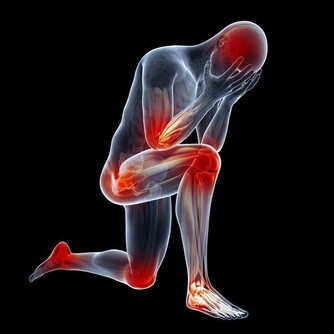

表現為肌肉或抽描,發生在腰部手臂或部。常呈對稱性,時而發作。患者意識醒,體溫一般正常。

通常發生在人進行劇烈運動目大量出時,人身體中的鹽分和水分隨汗液一同流失。肌肉中的含鹽量低可能是造成熱痙攣的原因。此外,停攣也可能是熱衰竭的一種表現。